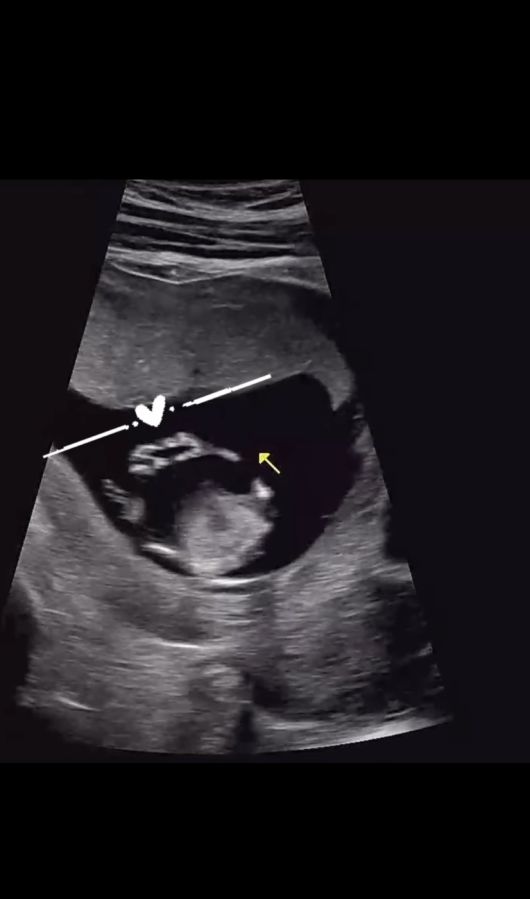

박가령은 지난 8일 자신의 SNS에 “여러분, 내가 엄마가 된다”는 글과 함께 임신 테스트기와 초음파 사진이 담긴 영상을 공개했다.

공개된 초음파 사진 속에는 아기가 마치 두 손으로 손하트를 만든 듯한 모습이 담겨 있어 많은 이들의 관심과 축하를 받았다.